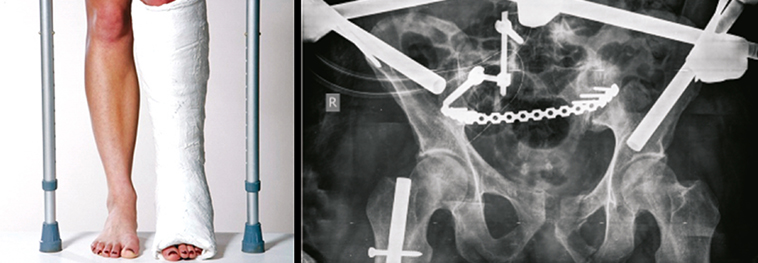

The Department of Orthopaedic Trauma and Emergency at Trustwell Institute of Musculoskeletal Sciences is a meticulously set up department in the entire hospital. Understanding the gravity of the situations in which patients arrive for immediate care, our department is ready to serve 24/7, 365 days, with courage and determination.

The Department is equipped with some of the best life support systems bringing in a fine mix of medical excellence and technology. Some of our speciality services at the hospital include,